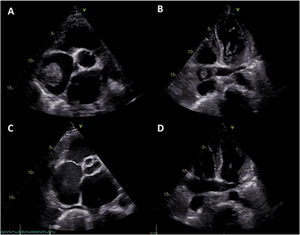

The electrocardiogram showed sinus rhythm with left atrial abnormality and positive electrocardiographic criteria for left ventricular hypertrophy. Computed tomography pulmonary angiography revealed pulmonary embolism (PE), with thrombi in the left segmental and subsegmental branches of the pulmonary artery and a 5-cm right atrial mass suggestive of thrombus (Figure 1A and B).

TTE showed severe mitral regurgitation caused by posterior leaflet prolapse, two mobile right atrial masses measuring 2.4 cm×1.5 cm and 3.6 cm×3.7 cm (Figure 1C), PASP of 70 mmHg, moderate dilatation of the right ventricle, reduced right ventricular function (tricuspid annular plane systolic excursion 16 mm) and preserved left ventricular function.